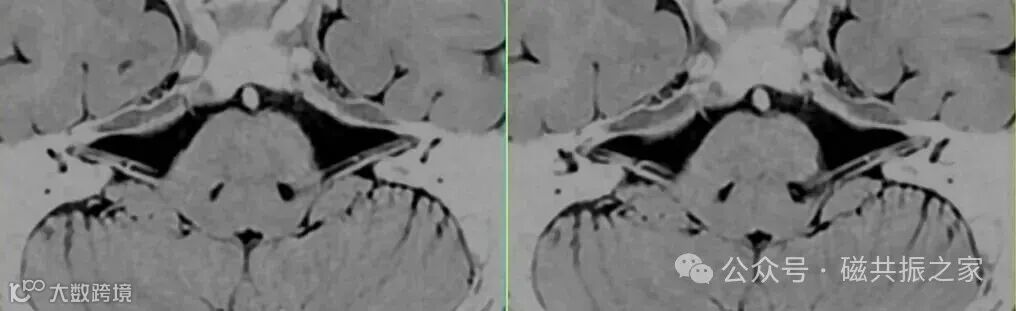

如上图△,左为基于梯度回波的3D 稳态自由进动序列;右为基于自旋回波的3D 重T2WI序列。

我们知道,IAC成像更强调的是水成像,如上图△为基于3D 重T2WI所获得的耳蜗结构图像。